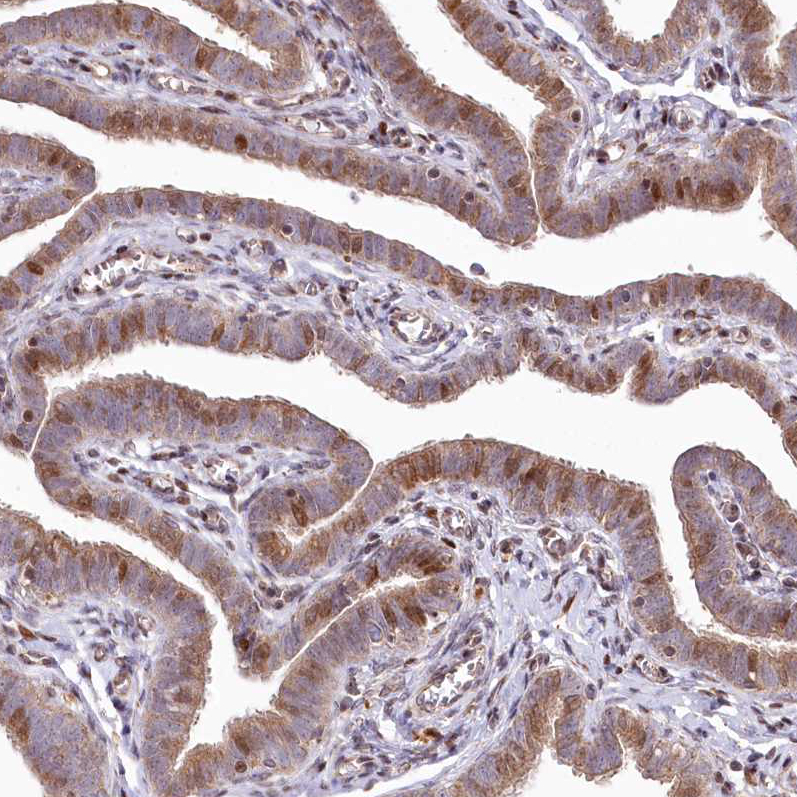

Immunohistochemical staining of human Testis shows strong granular cytoplasmic positivity in Leydig cells.